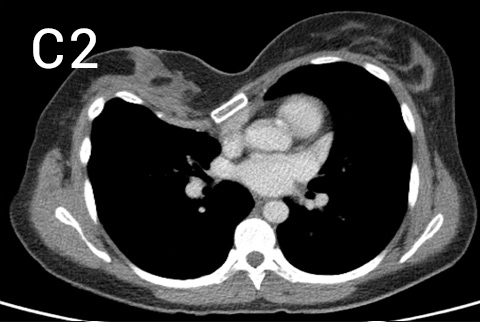

Pre-operative photos (A and B) with chest CT (C, multiple slices of upper (1), middle (2) and lower (3) chest) showing a long very asymmetrical pectus excavatum deformity in a 35 year old patient with striking symptoms of constrictive feeling in her chest